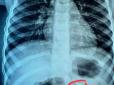

Майже 45% інфарктів протікають безсимптомно: Як розпізнати

Майже 45% інфарктів протікають майже безсимптомно. Їх ще називають "тихі серцеві напади". Як розпізнати та симптоми - читайте в матеріалі РБК-Україна (проект Styler), передають Патріоти України. Тихий серцевий напад - це стан, який не викликає симптомі...

Популярна іграшка вкрай небезпечна: У Франківську хірурги прооперували трирічну дитину, яка ковтнула 21 магніт

Медики Івано-Франківської обласної дитячої клінічної лікарні із шлунково-кишкового тракту трирічної дівчинки видалили 21 неодимовий магніт. Про це повідомив Департамент охорони здоров'я Івано-Франківської ОДА, передають Патріоти України. У медзаклад зв...